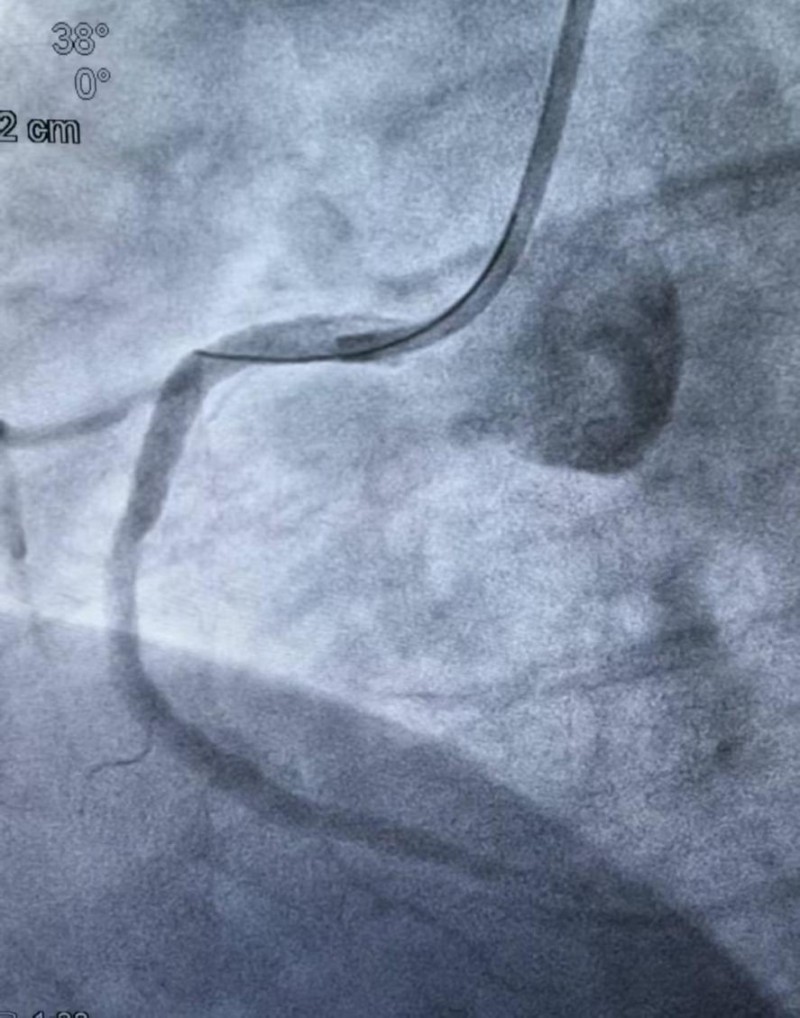

造影结果明确后,介入团队沉着应对,制定个体化方案,依次实施球囊扩张、血栓抽吸、冠脉内溶栓,精准清除血栓,解除血管闭塞,成功植入3枚支架,完全恢复冠脉血流,术后患者胸痛症状即刻缓解。

(术后)术后患者出现反复心衰发作,心血管内科团队立即启动